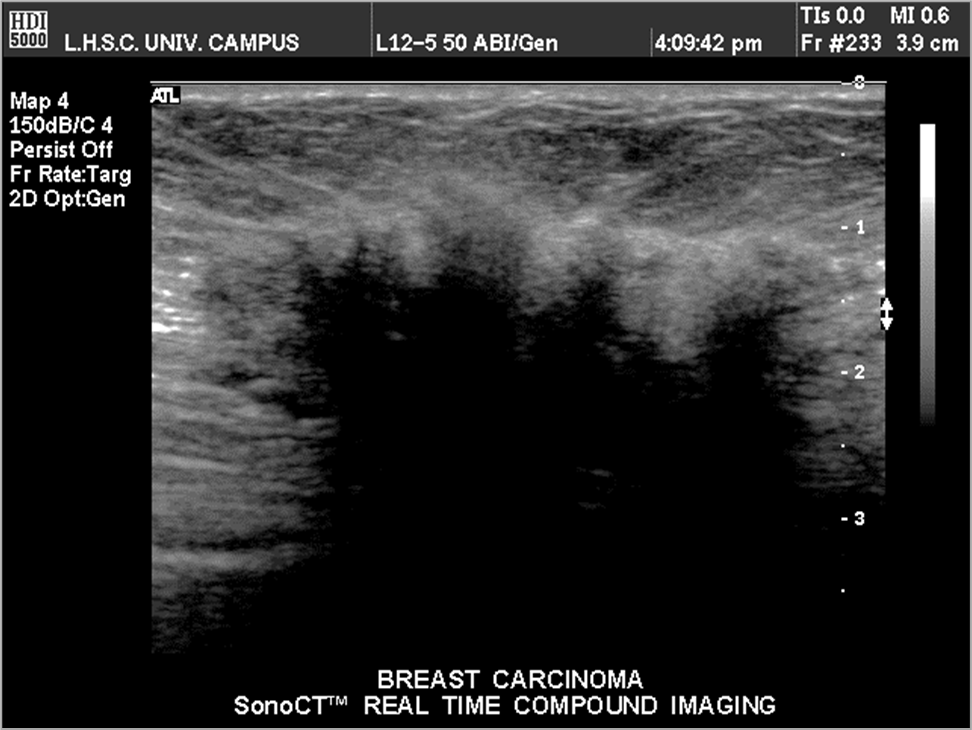

What is this image showing?

breast carcinoma

What are malignant characteristics?

irregular shape

attenuation shadowing hypoechoic or heterogeneous

taller than wide

fixed location

hard/fibrous